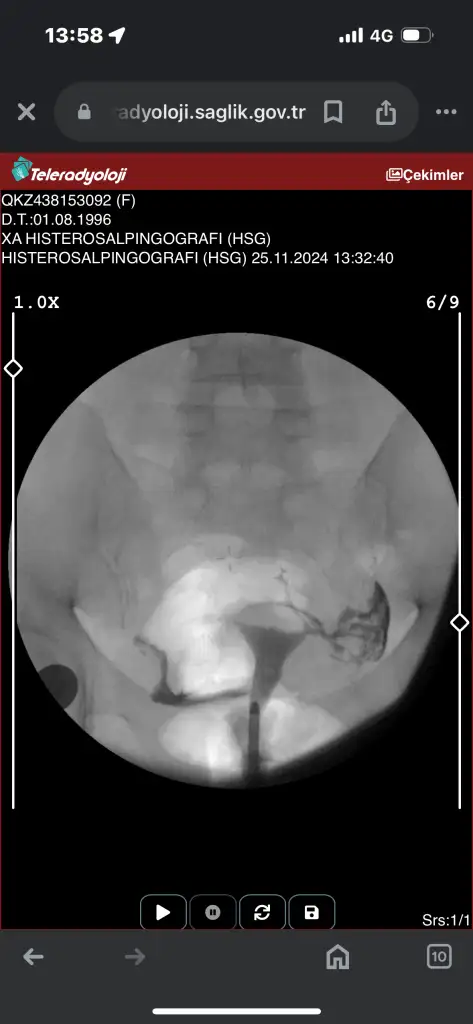

Canım tek tüpün kapalı galibaKızlar acil sonucuma bakarmısınızz ben hiçbirşey anlamıormm